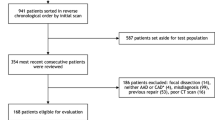

We retrospectively enrolled 378 patients who underwent non-contrast chest CT scans along with CT angiography or MRI from 4 medical centers. The training and validation sets were from 3 centers, while the external test set was from a 4th center. Radiomic features were extracted from non-contrast CT images. The radiomic signature was created on the basis of selected features by a logistic regression algorithm. The area under the curve (AUC) of the receiver operating characteristic (ROC) curve, accuracy, sensitivity, specificity, positive predictive value (PPV), and negative predictive value (NPV) were conducted to assess the predictive ability of radiomic signature.